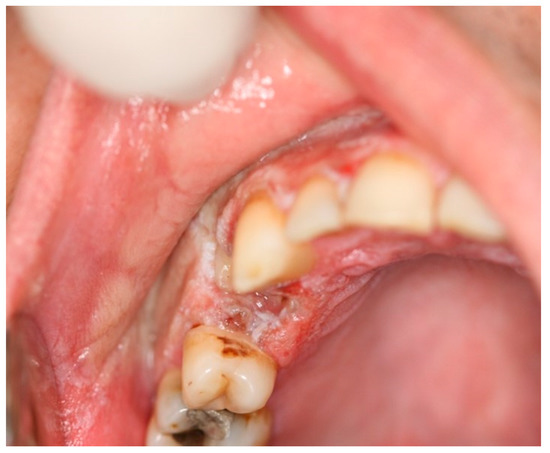

6.1. Frictional Keratosis

| Frictional keratosis | NA | NA | NA | white plaque with rough and frayed surface | removal of irritants | NA |